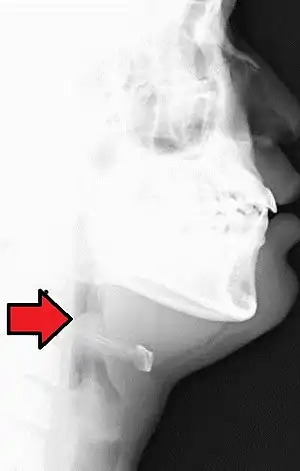

| Neck X-ray showing thumbprint sign. | |

Epiglottitis was historically mostly caused by infection by H. influenzae type b.[1] With vaccination it is now more often caused by other bacteria.[1] Other possible causes include burns and trauma to the area.[1] The most accurate way to make the diagnosis is to look directly at the epiglottis.[3] X-rays of the neck from the side may show a "thumbprint sign" but the lack of this sign does not mean the condition is absent.[1]

On lateral C-spine X-ray, the thumbprint sign describes a swollen, enlarged epiglottis.[10] A normal X-ray, however, does not exclude the diagnosis.[10] An ultrasound may be helpful if specific changes are present, but its use as of 2018 is in the early stages of study.[10]